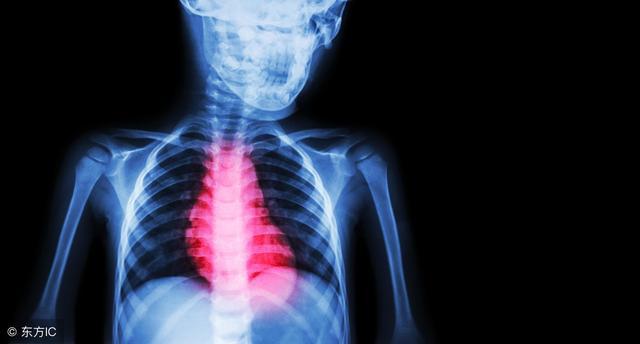

急性心肌梗死是由于持续而严重的心肌缺血所引起的部分心肌急性缺血性坏死。绝大多数急性心肌梗死的发生与冠状动脉粥样硬化斑块有关。这是因为冠状动脉出现粥样硬化斑块后,如同河流淤积了泥沙,使河道水流不畅,冠状动脉被完全阻塞,将造成断流,心肌好比河流所灌溉的农作物,就会因无水而枯死。

急性心肌梗死的临床表现为持久的胸痛、憋气、呼吸困难、心慌,严重者伴有严重的心律失常、急性心衰、休克、意识障碍,甚至发生猝死。